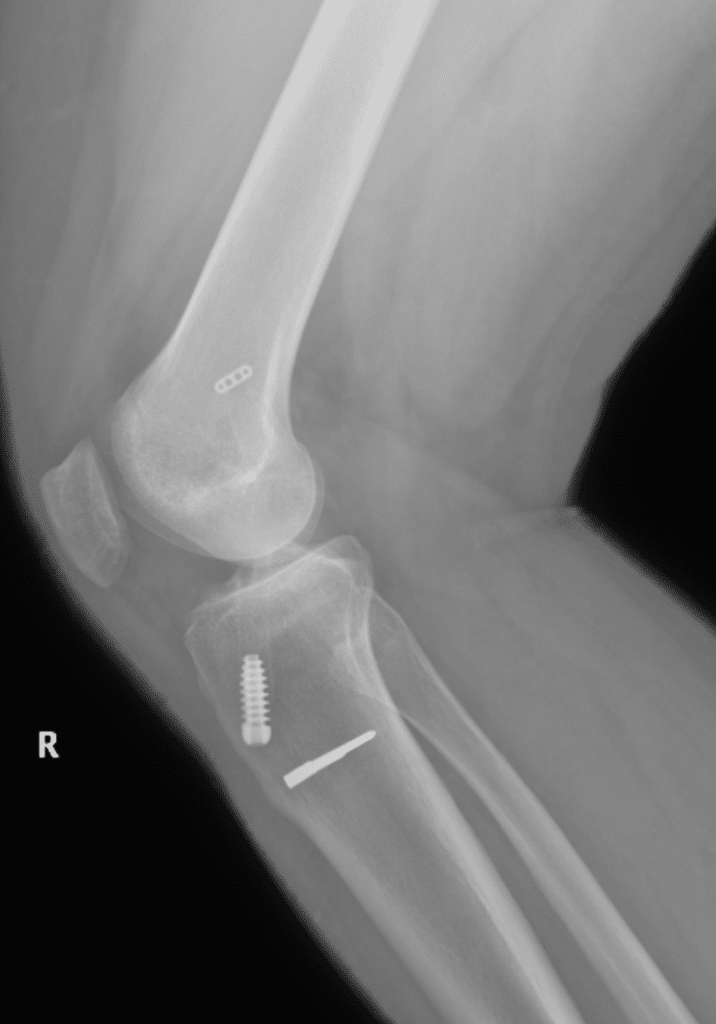

The surgery is completed with a combination of small incisions and arthroscopy assistance. Tissue for reconstruction is harvested from the same leg unless additional tissue is required. Synthetic graft or augments to graft may occasionally be used. The graft is secured through the knee joint with the use of staples and screws. Most patients go home the same day. Bruising and swelling are to be expected and elevation and Ice will help in the first 2-4 weeks.